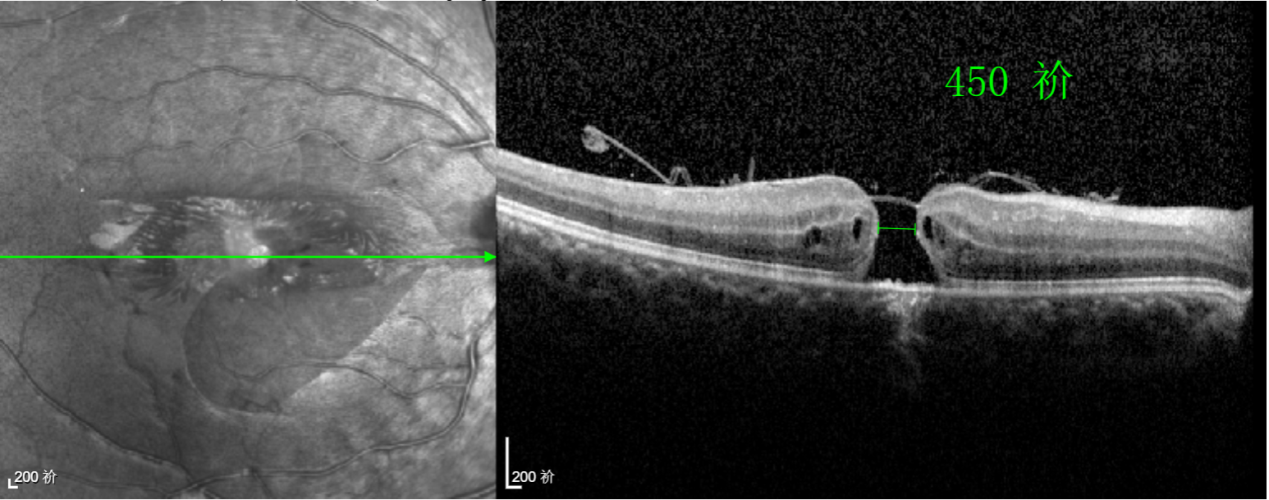

術(shù)中,醫(yī)生精細(xì)剝離黃斑區(qū)的內(nèi)界膜后,并非直接丟棄,而是巧妙地給它翻個(gè)面,讓它變成一塊天然“創(chuàng)可貼”,嚴(yán)密覆蓋在黃斑裂孔的表面。覆蓋的內(nèi)界膜像微型支架一樣撐住裂孔邊緣,防止它擴(kuò)大;同時(shí),這層膜本身含有能促進(jìn)生長(zhǎng)的“養(yǎng)分”,能顯著刺激裂孔周圍的視網(wǎng)膜組織像爬山虎一樣快速生長(zhǎng)、蔓延過(guò)來(lái),最終把裂孔“補(bǔ)”好。

除此之外,利用自體組織覆蓋為黃斑裂孔提供了理想的愈合環(huán)境,裂孔閉合速度顯著快于傳統(tǒng)方法。誠(chéng)誠(chéng)接受手術(shù)24小時(shí)后,檢查可見(jiàn)內(nèi)界膜瓣位置良好;術(shù)后1個(gè)月,黃斑裂孔已經(jīng)閉合,視力恢復(fù)到0.5;術(shù)后兩個(gè)月,視力進(jìn)一步提升到0.7。